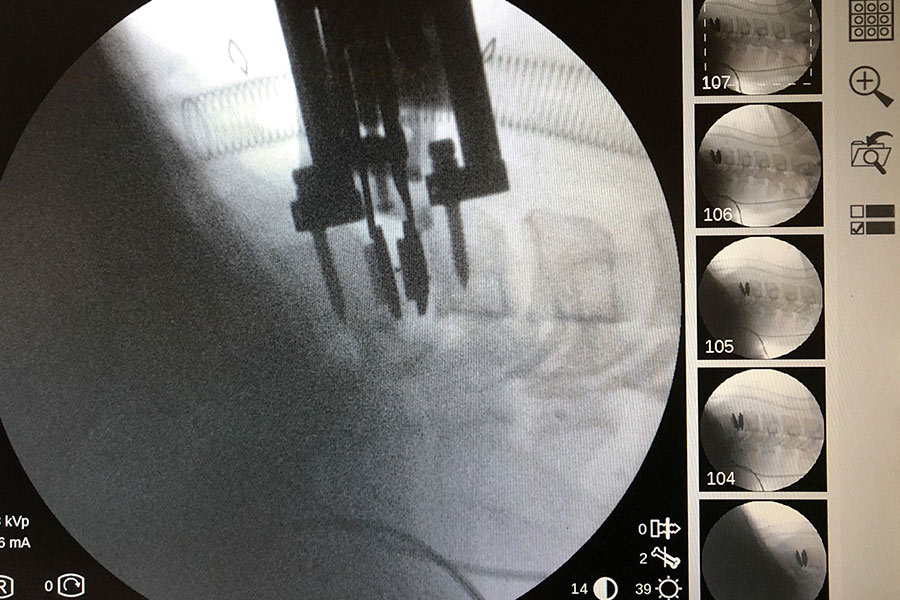

Se retira el implante intersomático y, tras una limpieza completa del ‘terreno’ tanto la parte intercervical como el canal, se implanta una prótesis cervical móvil.

postcirugia-protesis-cervical-compleja

Postoperatorio

El paciente sale de quirófano con una movilidad completa del cuello y la única recomendación de no coger peso durante la primera fase de recuperación para evitar posibles lesiones en la zona.